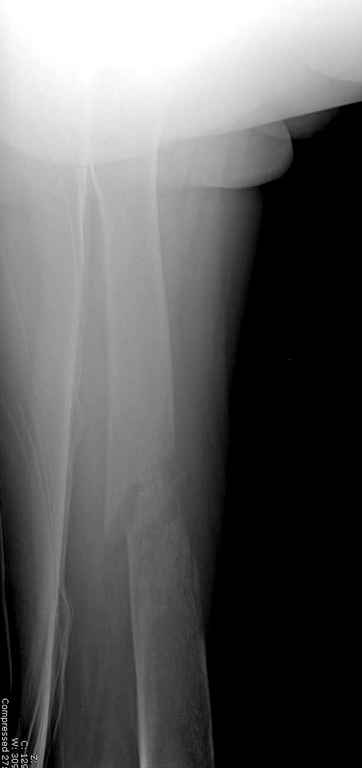

Здесь случай 66 летней пациентки со спонтанными болями в левой нижней конечности, обратилась в приемное, сделаны снимки бедра и КТ.

Патологический перелом бедра, конечность на вытяжении.

Известно, что многие из нас независимо от метода лечения и стадии первичной опухоли проводят интрамедуллярное штифтование при различных патологических состояниях бедра, включая патологические переломы.

В зависимости от характера опухоли некоторые патологические переломы имеют риск кровотечения во время операции. Множественные литературные данные подтверждают, что надо проявить осторожность при интрамедуллярном остеосинтезе при неизвестных опухолях, особенно где имеется подозрение на Renal Cell Carcinoma. (RCC- hypernephroma) http://www.bonetumor.org/tumors/pages/page64.html

Со слов, больная ничем не болела, только последние 3 месяцев чувствовала боли в бедренной области. КТ брюшной полости подтвердил увеличенную правую почку. (5-6)

Для предупреждения кровотечения во время рассверливания, за день до операции провели эмболизацию сосудов питающий метастаз. http://radiology.rsnajnls.org/cgi/reprint/150/3/673.pdf (7-11, 12-15-16)

С минимальным рассверливанием и ретроградным методом провели остеосинтез бедра 12 мм гвоздем. (17-20)

Кровопотеря во время операции меньше 100 мл.